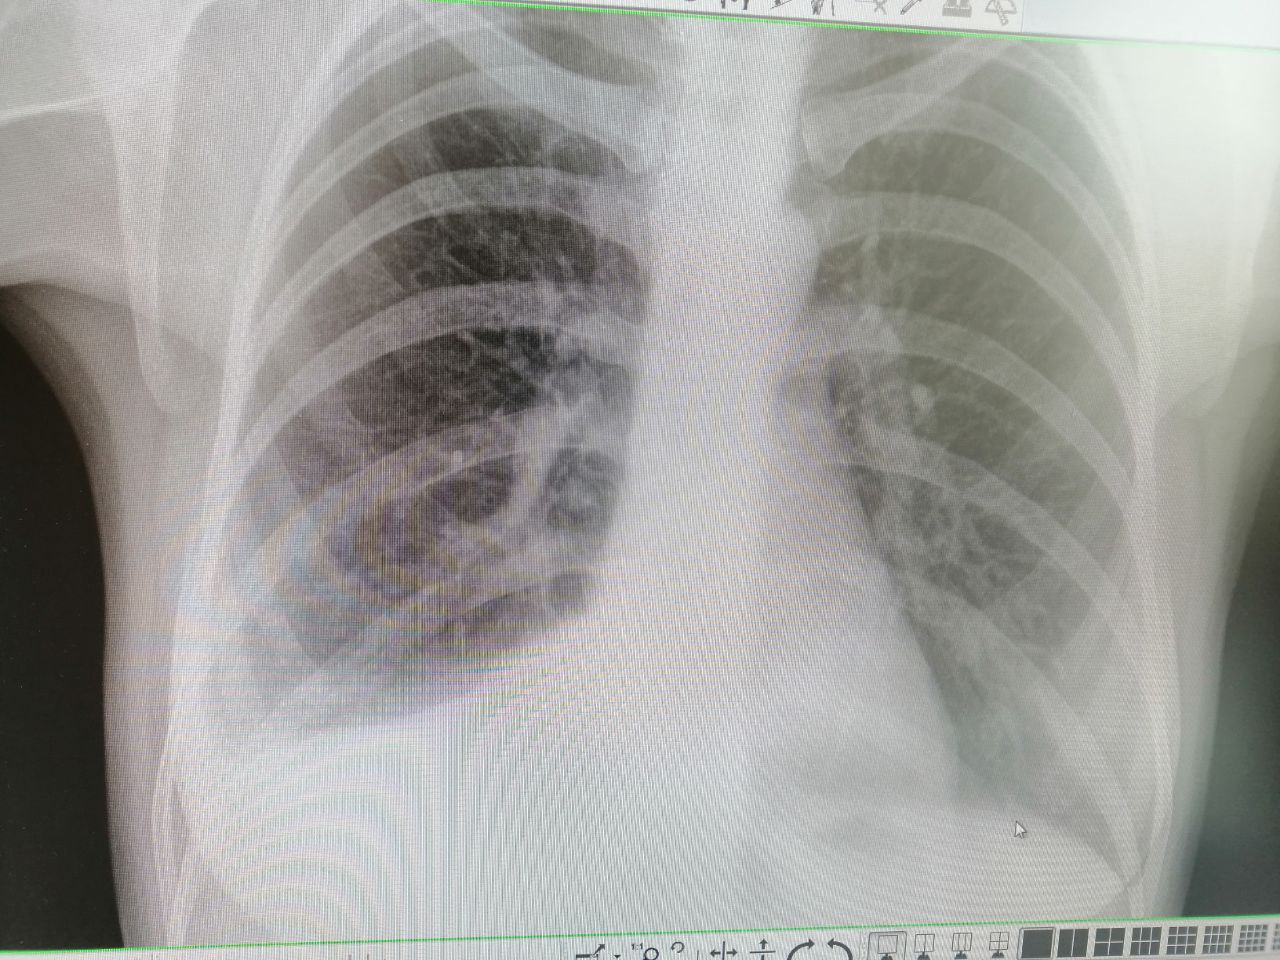

Нефиговый "малый" гидроторакс

Вот только написать хотела. Там нормально так жидкости

А на рентгене такого гидроторакса не видно.

Рентгенография и КТ с разницей 2-3 часа. Я сам в шоке...